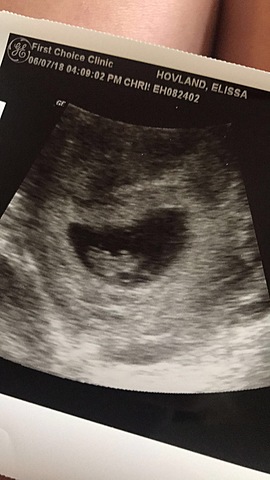

To be 110% sure that I was pregnant, I made an appointment at the First Choice Clinic in Fargo. At this appointment we did an ultrasound and saw that I was 5 weeks pregnant. They gave me an estimated due date of January 12, 2019.